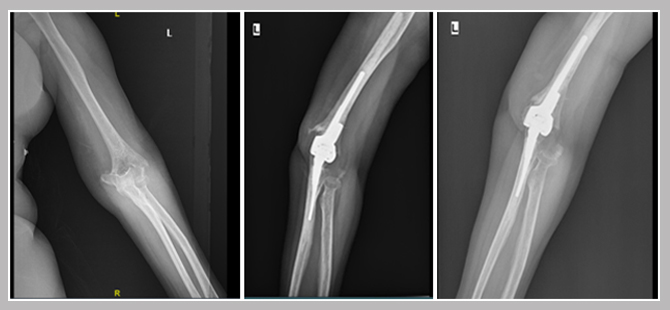

She underwent primary Total Elbow Replacement. In this surgery, the broken fragments are excised and a complex hinge type total joint prosthesis was implanted in arm and forearm bones together. After surgery, the arm was rested in splint for 24 hrs and from the next day she started full mobilization of elbow joint with the aid of physiotherapy.

She was advised to use the operated arm in her daily activities but to avoid heavy work and lifting. She regained full movement of her broken elbow joint in six weeks and was back to her routines. She was reviewed at every 3months interval. An x-ray taken 1yr post surgery shows no evidence of fracture. She also has no pain and can do full range of hand movements.